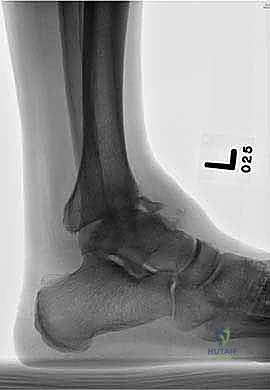

التصوير الطبي المتقدم (Medical Imaging)

لتأكيد التشخيص ووضع الخطة الجراحية، يتم الاعتماد على أحدث تقنيات التصوير:

- الأشعة السينية أثناء الوقوف (Weight-bearing X-rays): هي الفحص الذهبي والأهم. يجب أن تؤخذ الأشعة والمريض واقف لتحمل الوزن. تظهر الأشعة تضيق المسافة المفصلية (دليل على فقدان الغضروف)، وجود نتوءات عظمية، تصلب العظم، وأي انحراف في محور المفصل.

- التصوير المقطعي المحوسب (CT Scan): يطلبه الدكتور هطيف لتقييم جودة العظام (Bone stock)، تحديد حجم الأكياس العظمية، ورسم خريطة ثلاثية الأبعاد للتشوهات المعقدة قبل الجراحة.